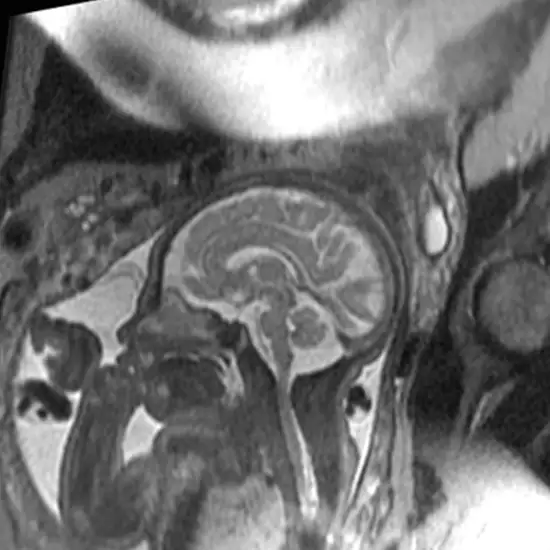

MRI Fetus checks fetus with greater detail of brain, spine, face and neck, lungs and chest. As per the reports, this imaging test proves better than normal ultrasound upon multiple terms.

An MRI scan of fetus is used to visualise your baby’s brain, spine, and body. The scan produces high-resolution images. The scan is generally used to confirm the ultrasound diagnosis in complex cases where additional information is needed. The MRI scan helps confirm abnormalities such as ventriculomegaly, abnormalities of the corpus callosum, and posterior fossa.